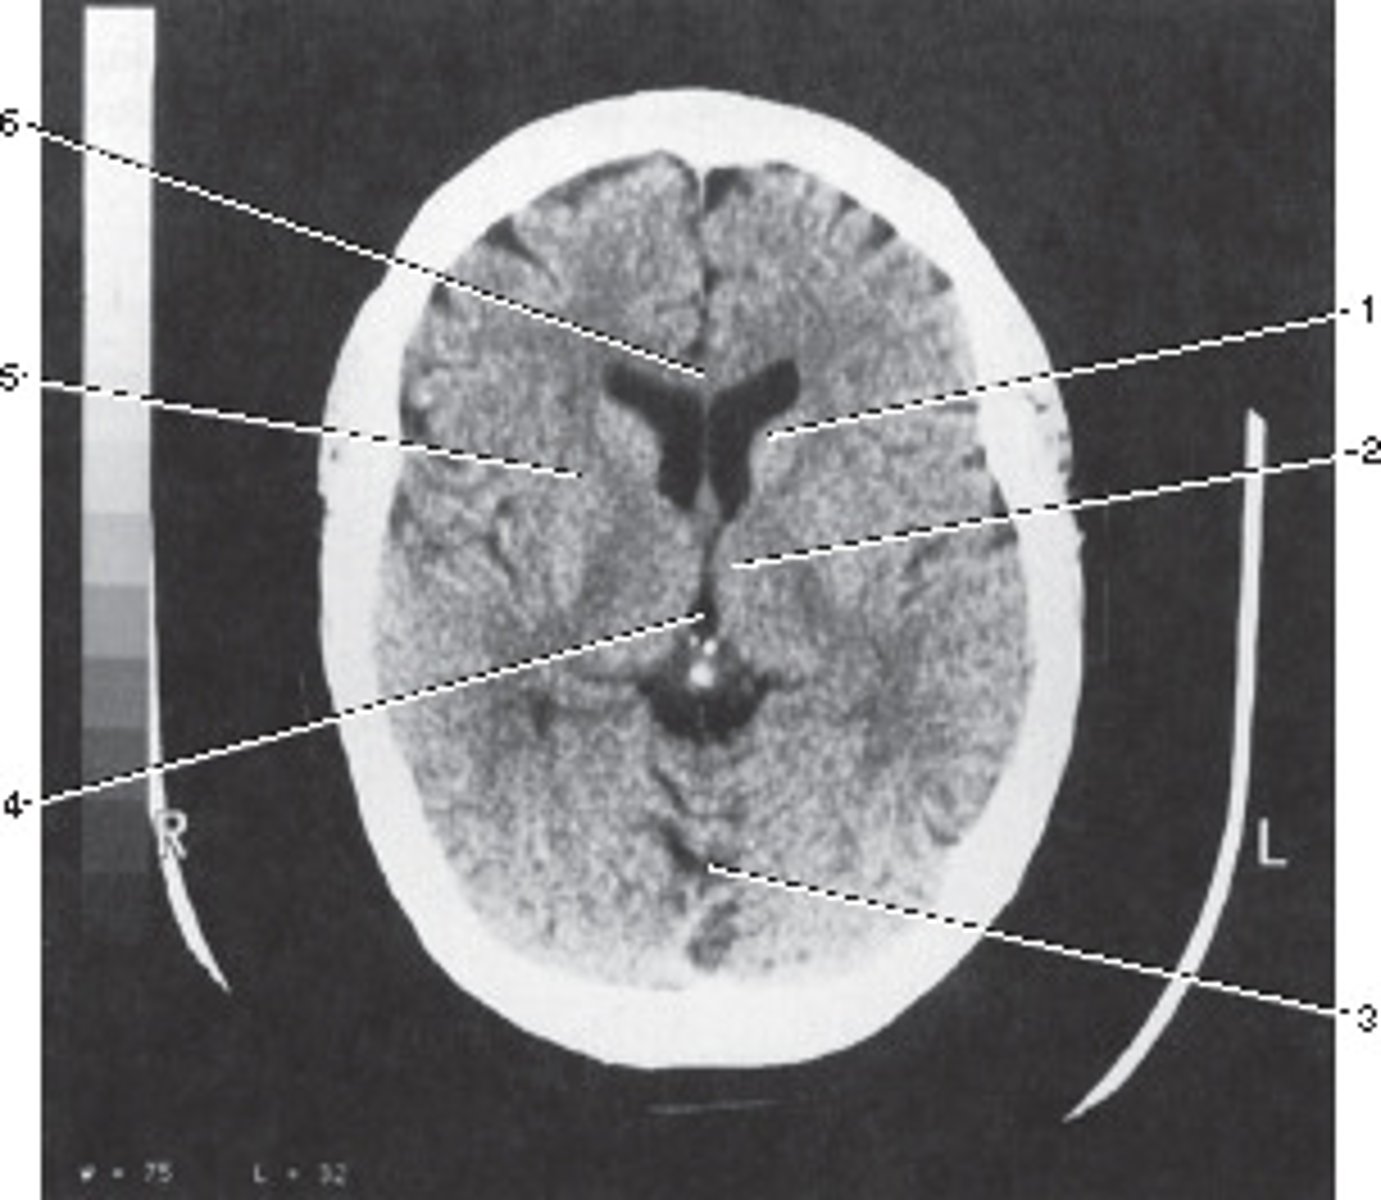

Third Ventricle

Number 4 corresponds to which of the following?

<p>Number 4 corresponds to which of the following?</p>

Genu of the Carpus Callosum

Number 6 corresponds to which of the following?

<p>Number 6 corresponds to which of the following?</p>